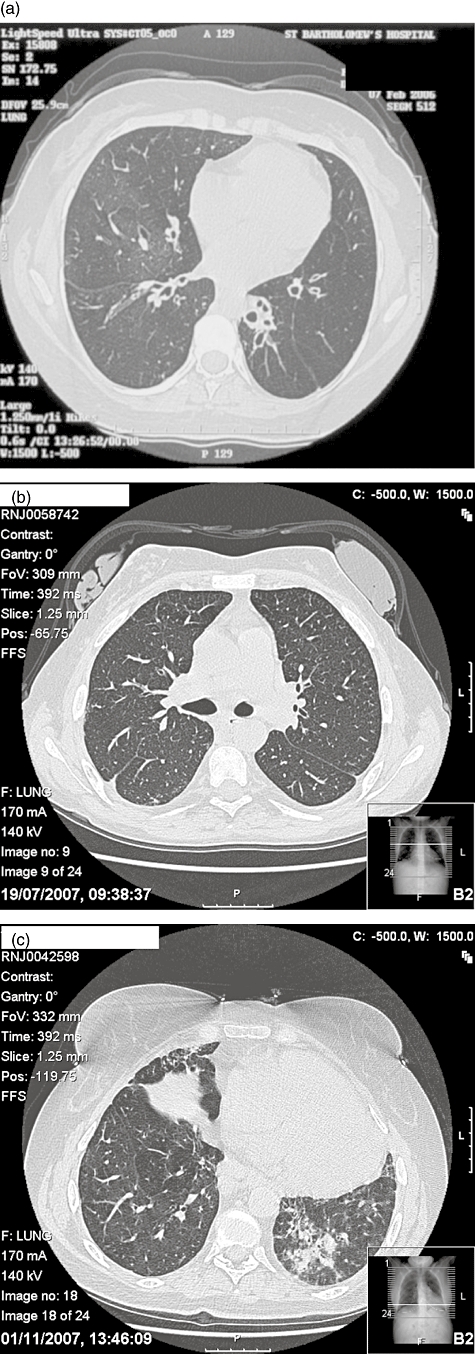

High-resolution computed tomography thorax (HRCT) is extremely sensitive and specific for the diagnosis and monitoring of bronchiectasis (Fig. 1a). Consensus on the indications for HRCT in PADS has not been achieved, and practice varies widely (Text box 2). Most physicians image the lungs routinely at baseline to assess the extent of chronic lung disease (including ILD, discussed later), but thereafter some prefer to scan only on the basis of clinical features while others scan at regular intervals, aiming to detect those with progressive damage. Various scoring systems have been devised to grade the severity of lung damage [26], attracting much interest as a surrogate marker for disease progression in CF trials; their value in the routine management of individual patients is undetermined. Compared with HRCT, the measurement of pulmonary function (PFTs) is relatively insensitive for the detection of early bronchiectasis, but is useful for monitoring the progression of chronic lung disease, providing guidance on the need for inhaled steroids and bronchodilators and assessing gas exchange which, if impaired, may suggest the possibility of ILD. Monitoring is recommended to detect complications, prompt further investigations and to alert the physician to the need for intensified or additional treatments.

Fig. 1.

(a)High-resolution computerized tomography (CT) scan of the chest of 33-year-old female common variable immunodeficiency (CVID) patient, showing bilateral bronchiectasis. (b)High-resolution CT scan of chest of 30-year-old female, with multi-organ granulomatous CVID, showing hilar lymphadenpoathy. (c)High-resolution CT scan of chest of 60-year-old female, with CVID and minimal respiratory symptoms. She had a restrictive defect on lung function monitoring. CT revealed hilar and subcarinal lymphadenopathy (not shown), left-sided volume loss, ground glass opacification and reticular shadowing suggestive of fibrosis.

The predominant symptoms of ILD in CVID patients are dyspnoea and reduced exercise tolerance. HRCT is the modality of choice for the diagnosis and monitoring of ILD [10,82]. A variety of findings have been described, including mediastinal lymphadenopathy, multiple ill-defined parenchymal nodules, usually with bronchocentric distribution, ground glass opacities and interseptal lines [20,83–85] (Fig. 1b and c).